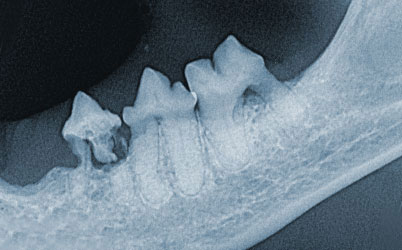

Viele unserer Patienten haben krankhafte Veränderungen an den Zähnen. Obwohl die Zähne von Hunden und Katzen, ebenso wie die Zähne des Menschen mit Schmerz­fasern versorgt sind, zeigen unsere Tiere häufig keine oder nur milde Anzeichen, die auf Zahnschmerzen hinweisen. Oftmals ist die Krone eines erkrankten Zahnes sogar einwandfrei. Erst durch das Zahnröntgen können die Schäden im Zahnwurzelbereich sichtbar gemacht und damit unseren Patienten nachhaltig geholfen werden.

Unsere Praxis verfügt über ein spezielles Zahnröntgengerät mit digitaler Bild­verarbeitung. Dieses System bietet hervorragende Bildqualität und ist zeitsparend, was sich wiederum vorteilhaft auf die Narkosedauer auswirkt. Bei einer Katze kann innerhalb von 10 Minuten ein Röntgenstatus des gesamten Gebisses erhoben werden. Aufgrund dieser Bilder kann zwischen Typ 1, Typ 2 und Typ 3 der sogenann­ten FORL´s (Feline odontoklastische resorptive Läsionen) unterschieden und ent­sprechend zielgerichtet therapiert werden.